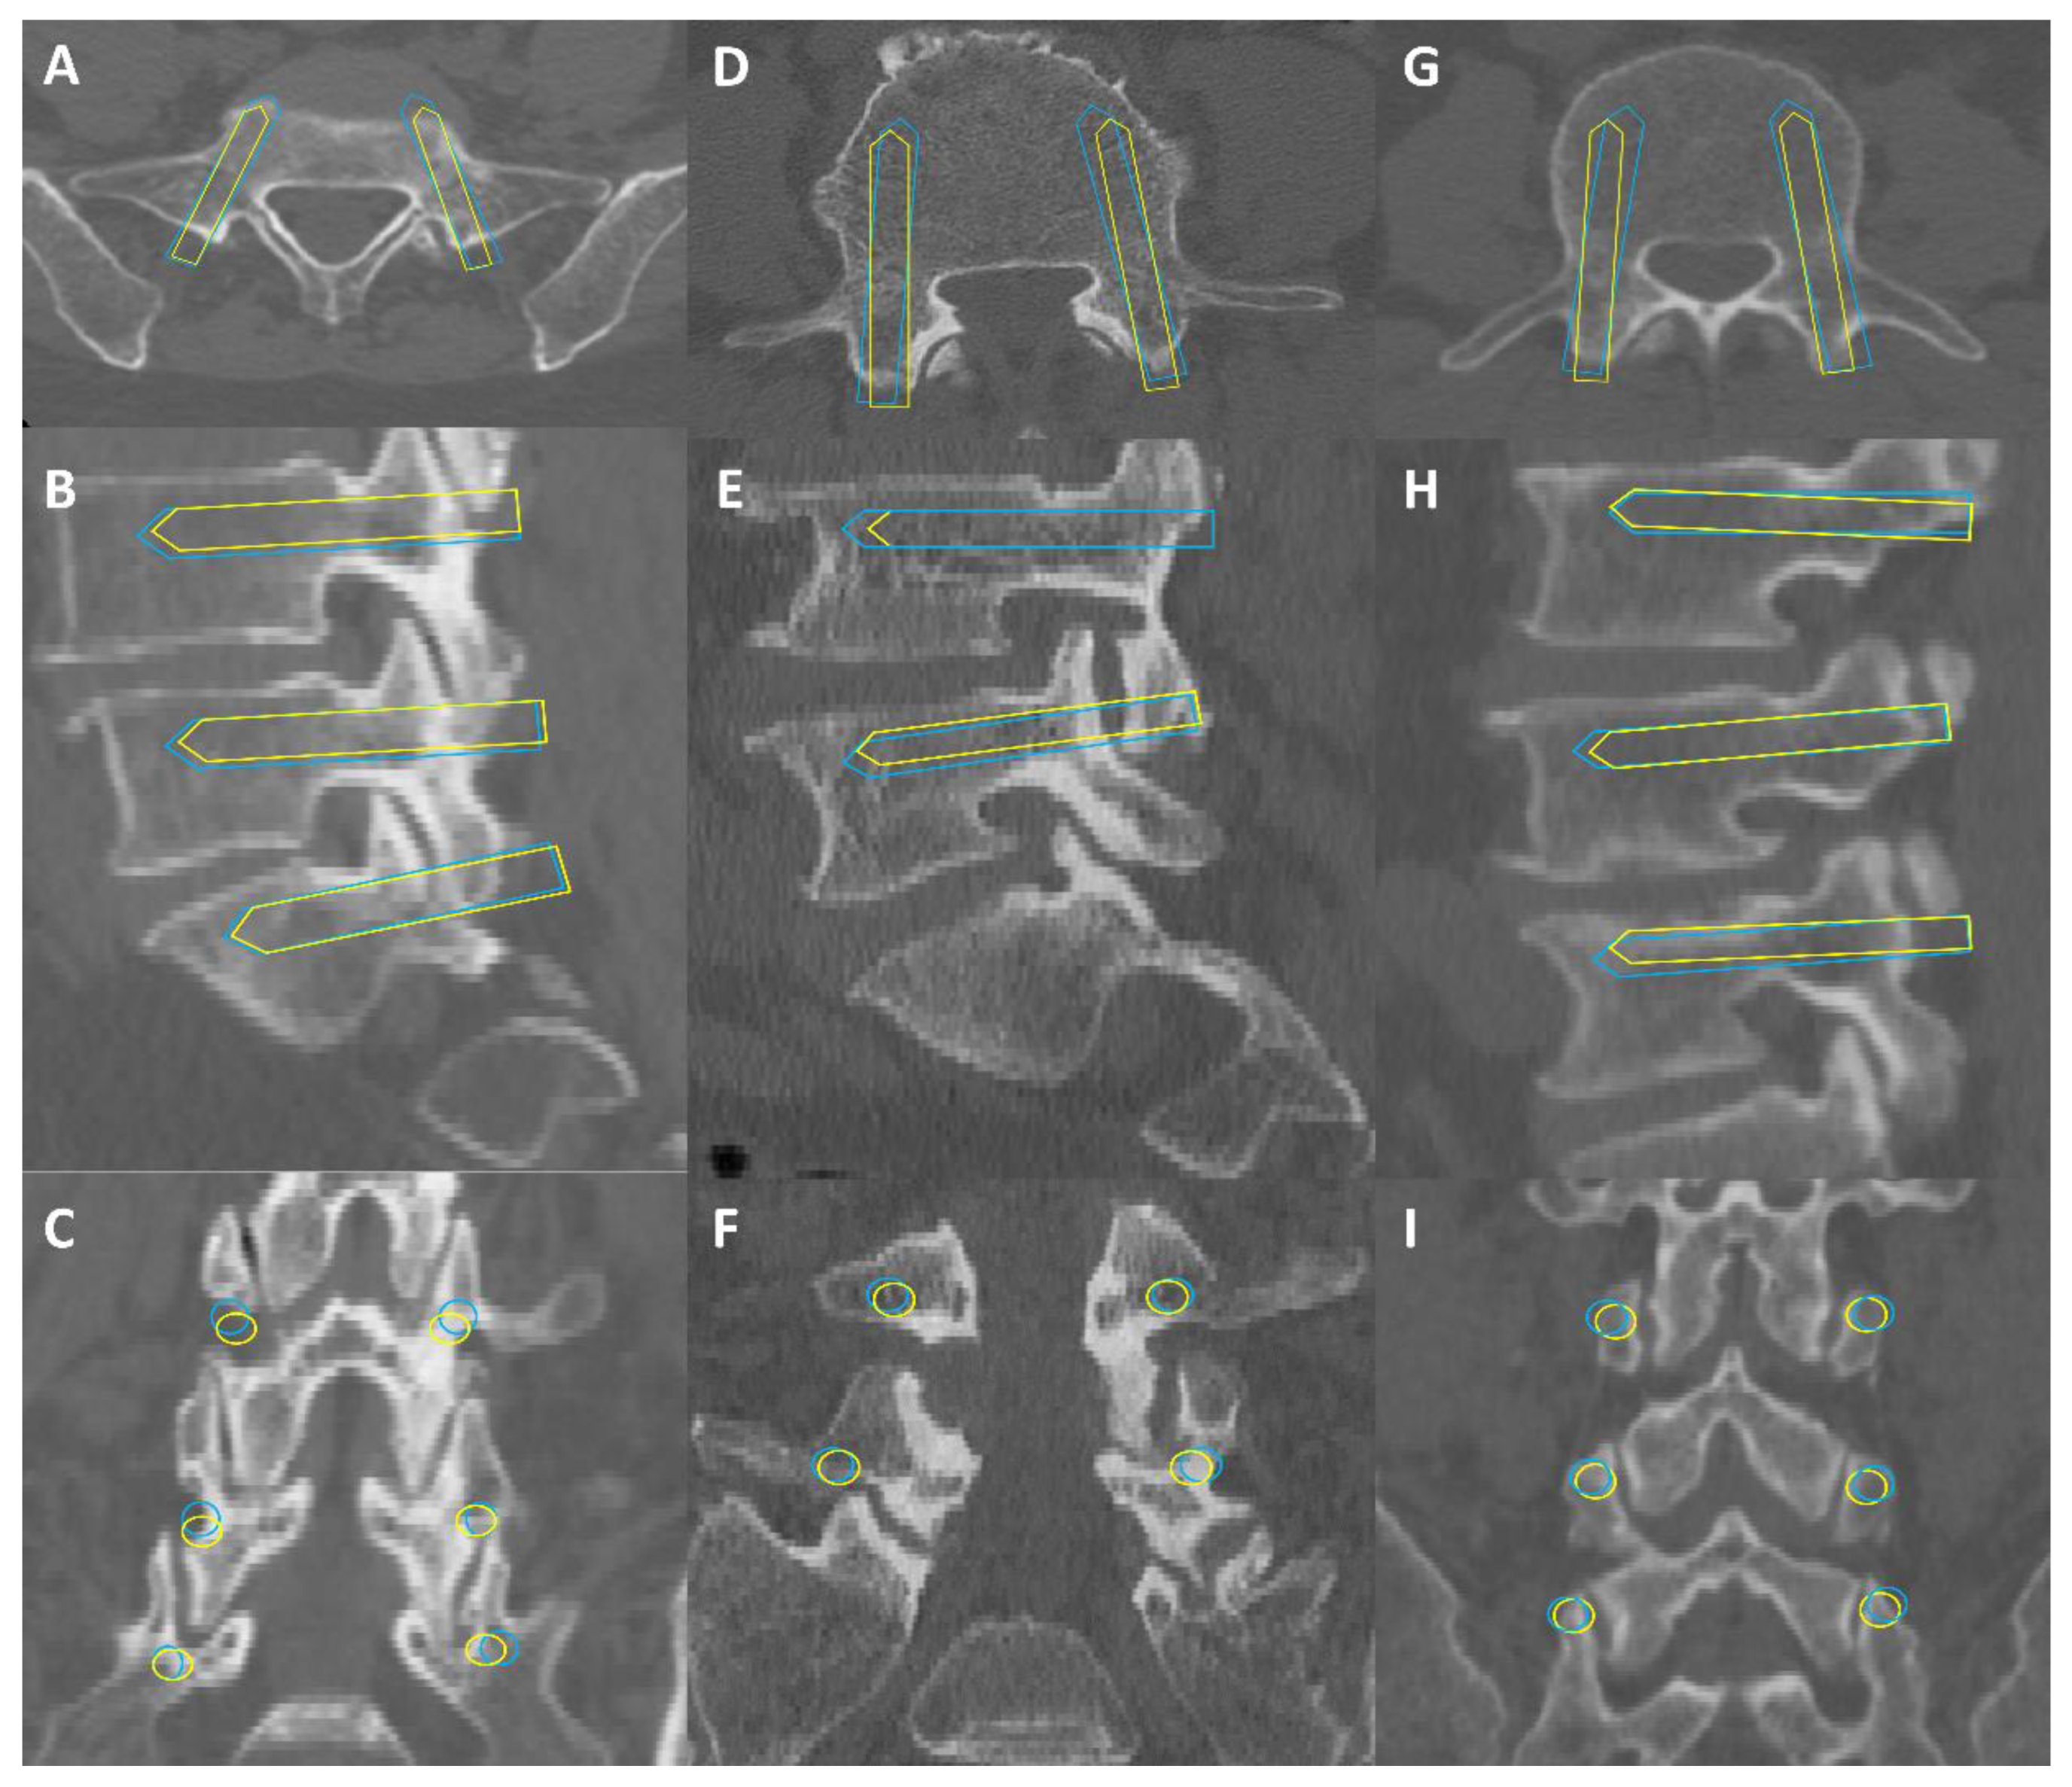

2.4.1. Image Segmentation

2.4.2. The Identification Model of Entry Point and Exit Point

2.4.3. Preoperative Planning Module